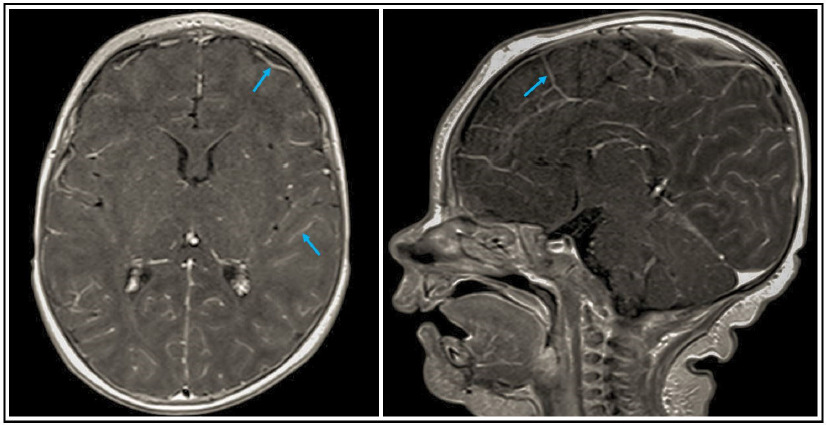

The child was first referred to the infectious diseases unit of our tertiary care university pediatric hospital at the age of 5 weeks because of fever of 39 degrees Celsius, apathy, and loss of appetite with a preliminary diagnosis of the neonatal sepsis. On admission, she presented with weakness, dehydration, pharyngitis, and stomatitis. However, there were no signs of abdominal organomegaly, lymphadenopathy, or meningismus during physical examination, and the lungs and heart were clear on auscultation. The infectious workup including blood cultures, tracheal aspirate, and blood real time-polymerase chain reaction (RT-PCR) viral and bacterial panels did not show any pathogens. In the cerebrospinal fluid, the parechovirus (HPeV)-RNA was detected thereby supporting the diagnosis of the neonatal sepsis-like illness with central nervous system (CNS) infection. The summary of an infectious workup performed in the patient is displayed in Table S1. The magnetic resonance imaging (MRI) examination with a contrast medium of the brain revealed abnormally increased enhancement of the leptomeninges (pia mater and arachnoid mater). The results of cerebral MRI consistent with meningitis are shown in Supplemental Figure 1. Because of hypogammaglobulinemia regarding all isotypes, IgG 230 mg/dL (N:270-780), IgA 2 mg/dL (N:6-58), and IgM 11 mg/dL (N:12-87), and anemia, hemoglobin 8.8 g/dL and red blood cell count 2.7x106/mcL, transfusions of intravenous immunoglobulins and packed red blood cells were indicated. She recovered completely and her further psychomotor development was age-appropriate. She was vaccinated according to the national vaccination program with the live Bacille Calmette-Guerin (BCG) and anti-hepatitis B vaccines after birth, and then she continued the vaccination schedule with anti-tetanus, anti-diphtheria, inactivated poliomyelitis vaccine (IPV), and as a 13-month-old girl, she was vaccinated with a trivalent measles–mumps–rubella live vaccine without adverse effects following immunization (AEFI). At the age of 8 months, the girl was hospitalized in the department of pediatric nephrology for Proteus mirabilis urosepsis. Thereafter, by the age of 3 years, she suffered from recurrent urinary tract infections. Since the end of the first year of life, the girl also presented with recurrent respiratory tract infections: pneumonia, bronchitis, otitis media, tonsillitis, and laryngitis, requiring antibiotic therapy 6–8 times every year.

Figure 1 Cerebral MRI examination with a contrast medium showing abnormal increased enhancement of leptomeninges, pia, and arachnoid maters (marked with arrows).